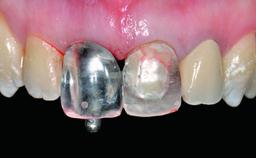

A 32-year-old female Caucasian patient with a compromised maxillary right central incisor was referred to us by a general dentist. Her chief complaints were discomfort and mobility of tooth 11 with unsatisfactory esthetics due to discoloration. The patient reported a previous trauma, some years earlier, as the origin of pathology on the afflicted tooth. Anamnesis was negative for any other dental or periodontal pathology in the remaining dentition. The patient did not take any medication and reported to be a light smoker (5–10 cigs/day). She had high esthetic expectations of her treatment. The extraoral examination revealed a high smile line with full exposure of her maxillary teeth and surrounding soft tissue in the area between the second premolars.

Placement Protocol Early or late implant placement